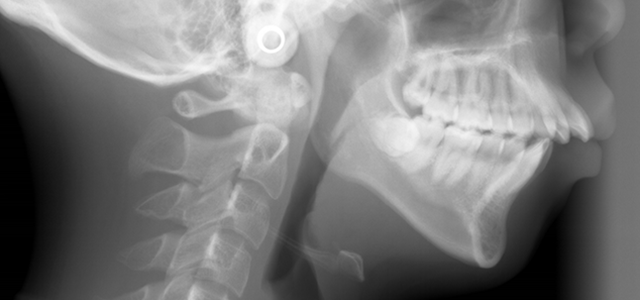

矯正前 パノラマX線

矯正後 パノラマX線

主訴 前歯で物が咬めない、歯並びの凸凹、出っ歯を治したい

年齢 20代

治療法 上下顎マルチブラケット装置、歯科矯正用アンカースクリュー

抜歯の有無 上顎左右側第一小臼歯、下顎左右側第二小臼歯